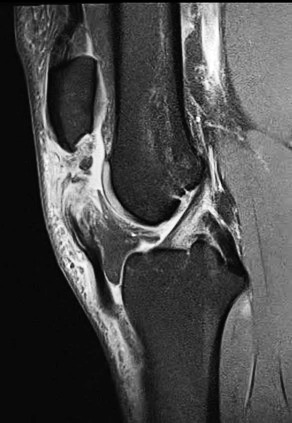

Patellar tendon rupture is a devastating injury and occurs in approximately one per 100,000 knees (for any reason). (Figure 1) Following primary total knee arthroplasty (TKA), patellar tendon rupture approaches an incidence of 2.5%, and > 5.0% following revision TKA (Vaishya et al. 2016).

This is 74-year-old female, with a BMI of 33 kg/cm2, and multiple comorbidities (CHF, Arrhythmia, anxiety, 3 previous surgeries of the knee). She presented three months status post patellar tendon rupture, patellar fracture and dislocation. The patellar fracture was fixed with a wire, and in the radiograph you can see the anchor suture in the tibial tubercle area, the wire below the tubercle, within the gutters, and threaded above the patella. (Figure 8)